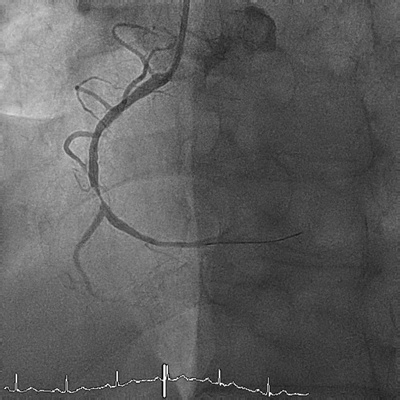

Koronare Herzkrankheit

Die koronare Herzkrankheit zählt zu den häufigsten Erkrankungen des Herz-Kreislauf-Systems. An ihren Folgen sterben in Industriestaaten mehr Menschen als an jeder anderen Krankheit. Wird eine koronare Herzkrankheit jedoch frühzeitig behandelt, haben Betroffene eine gute Prognose.

Häufig und gefährlich, aber gut behandelbar

Ein verengtes Herzkranzgefäss führt dazu, dass das Blut nicht mehr ungehindert hindurchfliessen kann.